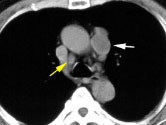

Scott WilliamsHomeCHEST > Tumor > Malignant > Lungcancer > StagingApril 2, 2002HomeCHEST > Tumor > Malignant > Lungcancer > StagingApril 2, 2002HomeCHEST > Tumor > Malignant > Lungcancer > StagingApril 2, 2002HomeNucMed > PET > PET tumor imaging > GeneralApril 2, 2002PETPET > PET tumor imaging > GeneralApril 2, 2002PETPET > PET tumor imaging > GeneralApril 2, 2002PETPET > PET tumor imaging > GeneralApril 2, 2002CardiacCardiac > Adultdz > Atrial FibrillationApril 2, 2002RIARIAApril 2, 2002RIARIAApril 2, 2002Previous PagePage 33 of 265Next PageTop StoriesMolecular ImagingPET predicts faster cognitive decline in women than menWomen initially outperformed men at low brain tau levels, but the advantage diminished as tau levels increased over time.MRIUnclear explanations of contrast MRI exams heighten patient anxietyWomens ImagingMammography screening improves survival for late-stage cancersUltrasoundUltrasound MinnieCast, Episode 2: Body imaging with RUS-PATSponsor ContentHow Agentic AI Is Transforming Radiology Ops